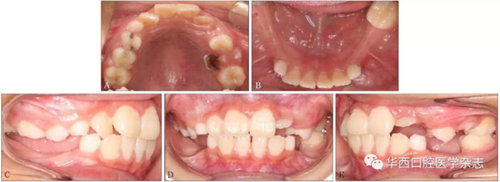

經過綜合分析及考慮患者的意愿,制定開窗-正畸協同治療方案,術前拔除尚未萌出的45牙為牽引46牙提供間隙,通過鑄造板將36、73、32、31、42、41、83牙連接成一整體,為牽引46牙提供支抗(圖4)。

A:右側像;B:正面像;C:左側像;D:下頜面像。

圖  4    矯治器初裝口內像

46牙開窗并將舌側扣粘接于近中面。用玻璃離子將鑄造板粘接在下頜,橡皮鏈通過83牙遠中的牽引鉤和46牙上的舌側扣相連,橡皮鏈牽引時對46牙產生一個順時針旋轉的作用力。術中牽引1個月時,見46牙產生順時針旋轉(圖5、6)。治療5個月時,46牙產生明顯的順時針旋轉,基本直立(圖7),由于此時下頜雙側乳尖牙脫落,下頜鑄造板無法固位,于是拆除矯治器,觀察隨診,待后期其余牙齒萌出后行全口固定正畸矯治。